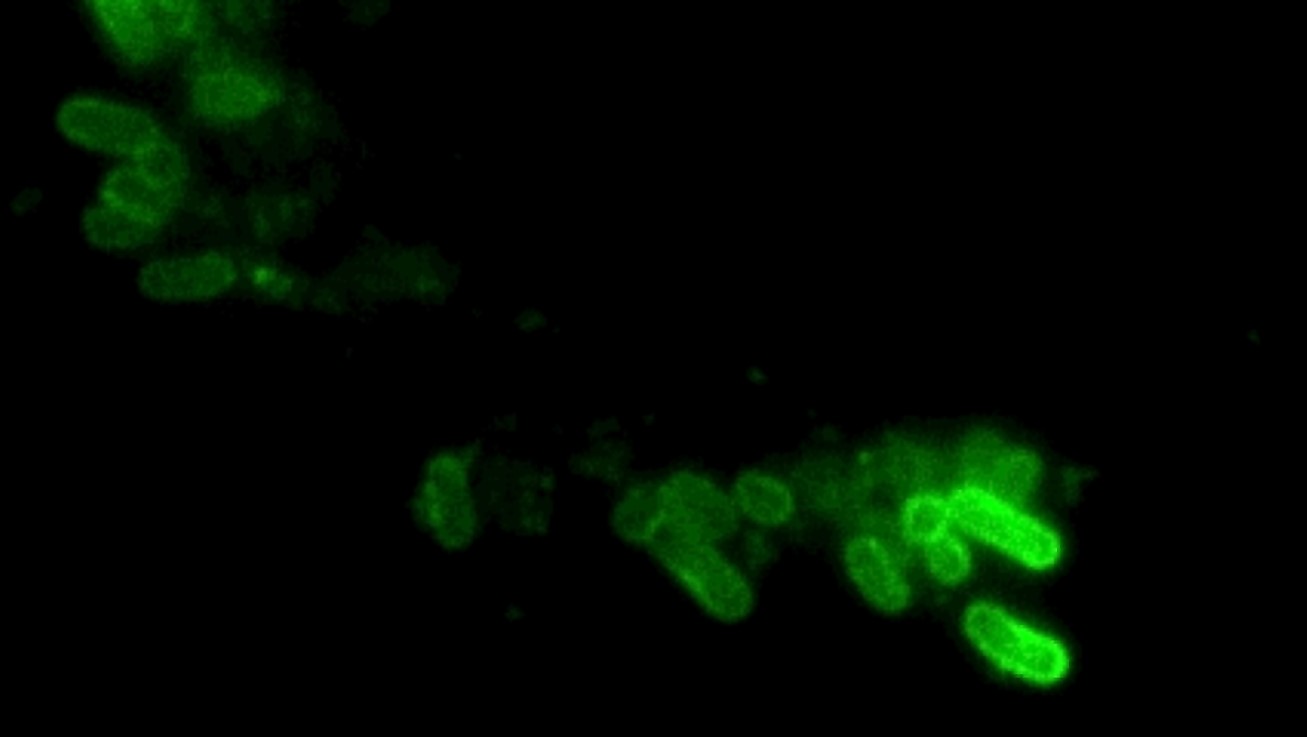

Investigadores del Consejo Superior de Investigaciones Científicas (CSIC) en el Centro Nacional de Biotecnología (CNB) han identificado un nuevo mecanismo molecular implicado en el desarrollo de la forma de la bacteria salmonela. Los resultados de este trabajo, que aparecen publicados en la revista Communications Biology, podrían servir como base para el diseño de tratamientos efectivos frente a las infecciones intracelulares persistentes causadas por esta bacteria.

A diferencia de algunas bacterias patógenas que alteran su forma en el hospedador, lo que dificulta su ingestión por células de defensa, este trabajo demuestra que Salmonella mantiene su forma bacilar ("de varilla") durante la infección. La morfogénesis celular es un proceso altamente regulado y dependiente de la estructura del peptidoglicano, un polímero que, a modo de corset, cubre por entero la célula y, además de proteger su integridad, la dota de una forma concreta.

La investigación detalla los sistemas con los que la bacteria logra persistir de forma prolongada en ambientes tan ácidos como el fagosoma celular. Sónia Castanheira, investigadora del CNB-CSIC, destaca: “En Salmonella hay dos tipos de PBP2, una PBP2 similar a la de E. coli y la PBP2SAL, esta última ausente en E. coli y en bacterias de la microbiota intestinal. Cada una de ellas se ha especializado para actuar bien fuera de la célula hospedadora a pH neutro (PBP2) o dentro del fagosoma acídico donde reside el patógeno en la infección intracelular (PBP2SAL)”

Según los científicos, sorprende que dicha especialización en respuesta a determinados ambientes se dirija, en el caso de Salmonella, a mantener una misma forma celular. Estas observaciones apuntan a que la forma celular no es casual. Así, determinadas bacterias habrían evolucionado adquiriendo proteínas adicionales para garantizar la conservación de su forma cuando se adaptan a ambientes tan particulares como el fagosoma ácido de la célula eucariota.